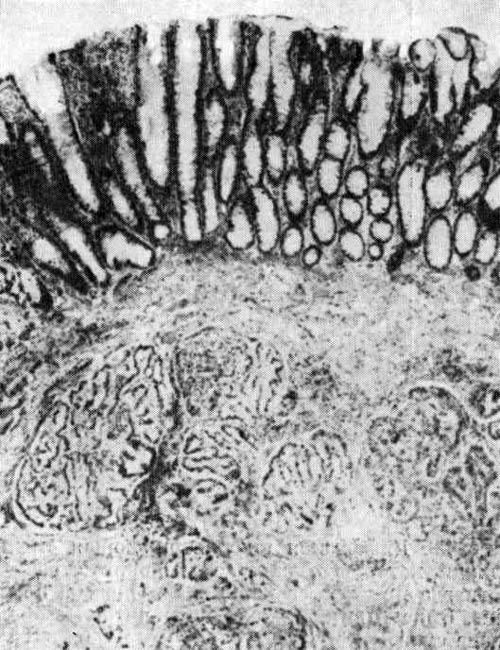

Вероятно, в большинстве случаев, если не всегда, рак толстой кишки развивается из аденоматозных полипов пли из аденоматозно измененной слизистой оболочки. Так называемые аденоматозные полипы характеризуются тубулярными структурами, а ворсинчатые опухоли имеют нежные папоротникообразные ворсинки. Эти структуры часто сочетаются в одном и том же полипе, и в настоящее время доказано, что эти два типа полипов трудно …

Лимфатическая сеть и капилляры в полипах и нормальной слизистой оболочке изучены С. Fenoglio и сотр. Они представали логическое обоснование отсутствия метастазов в лимфатические узлы при раке в пределах слизистой оболочки. Лимфатические сосуды подходят к основанию крипт и не распространяются поверхностнее даже при измененной архитектонике желез в аденоматозных полипах. Только при инвазии раковых клеток в мышечный …